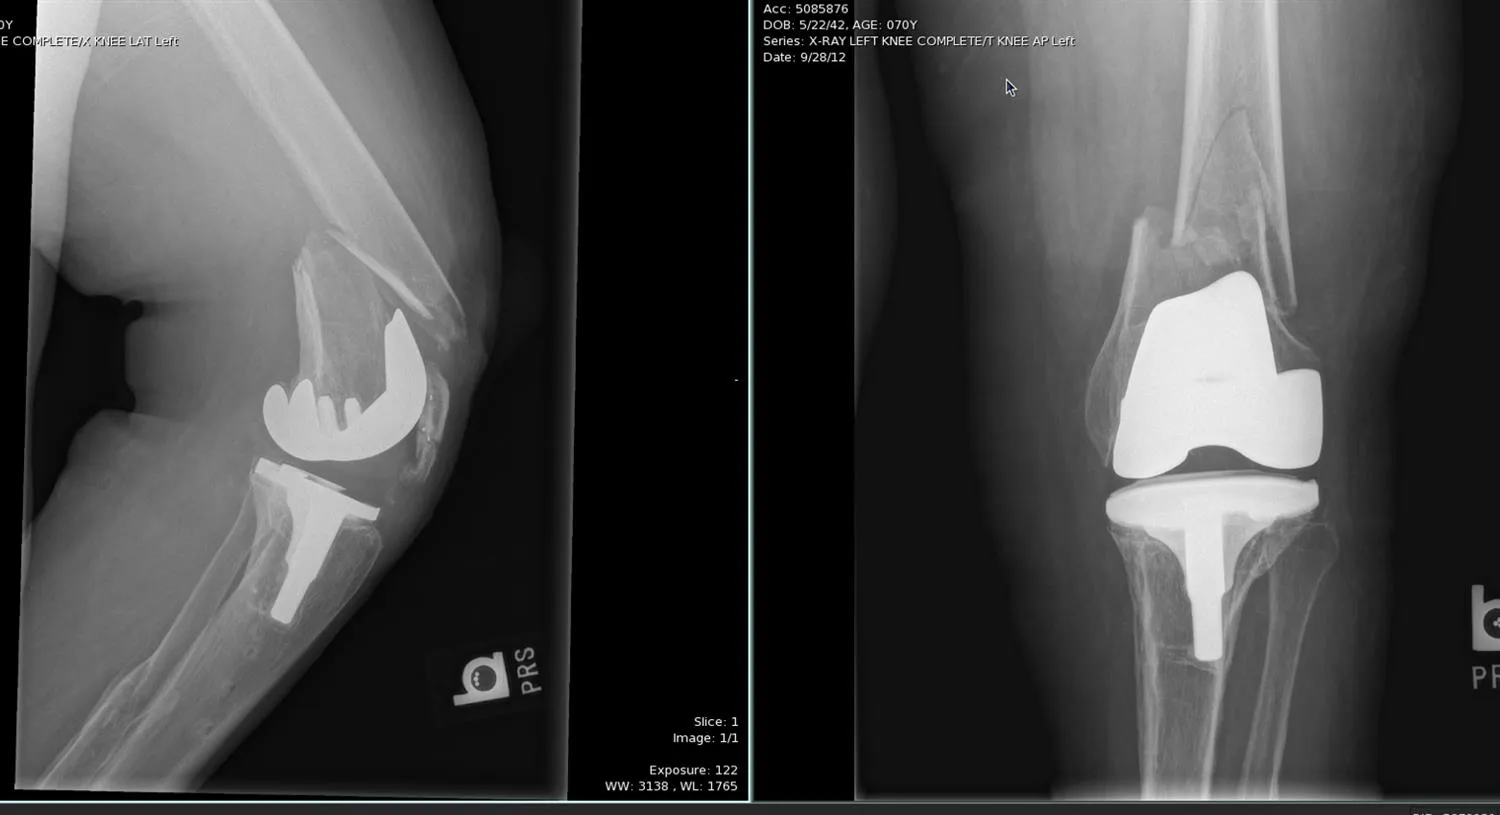

Röntgenfoto’s: Hierop kan men de prothese zien en de breuk eromheen. Vaak betreft het een femurfractuur net boven de femurcomponent (bovenste deel van de prothese): de röntgenfoto laat een fractuurlijn boven de metalen component zien en soms ziet men dat de prothesecomponent een andere positie heeft (als hij los is geraakt). Voor tibiafracturen (onderbeen) ziet men een lijn onder de tibiale component van de prothese.

CT-scan: Een CT kan helpen om de breukpatronen beter in kaart te brengen en om te beoordelen of de prothesecomponenten los zijn.

Een periprothetische kniefractuur is een uitdagende breuk waarbij het bot rondom een knieprothese breekt, meestal bij oudere patiënten na een val. Het presenteert zich met acute knie- en bovenbeenpijn, onvermogen om te steunen en vaak een instabiel gevoel in de kunstknie. Diagnostiek gebeurt via röntgen en een CT-scan om de fractuur en de status van de prothese in beeld te brengen. De behandeling is overwegend chirurgisch: als de knieprothese vastzit, probeert men de breuk te fixeren met platen/schroeven en de prothese te behouden; zit de prothese los of is de breuk complex, dan wordt een revisieprothese geplaatst die het defect overbrugt. De revalidatie is intensief en langdurig, en complicatierisico’s zijn reëel. Dankzij moderne technieken en ervaring is de uitkomst meestal goed. Patiënten moeten wel rekenen op een maandenlange revalidatie en mogelijk blijvende beperkingen zoals verminderde wandelafstand of nood aan loophulpmiddelen. Het voornaamste doel is dat de patiënt terugkeert naar een zo hoog mogelijke graad van zelfstandigheid, met een goed functionerende knieprothese na genezing.